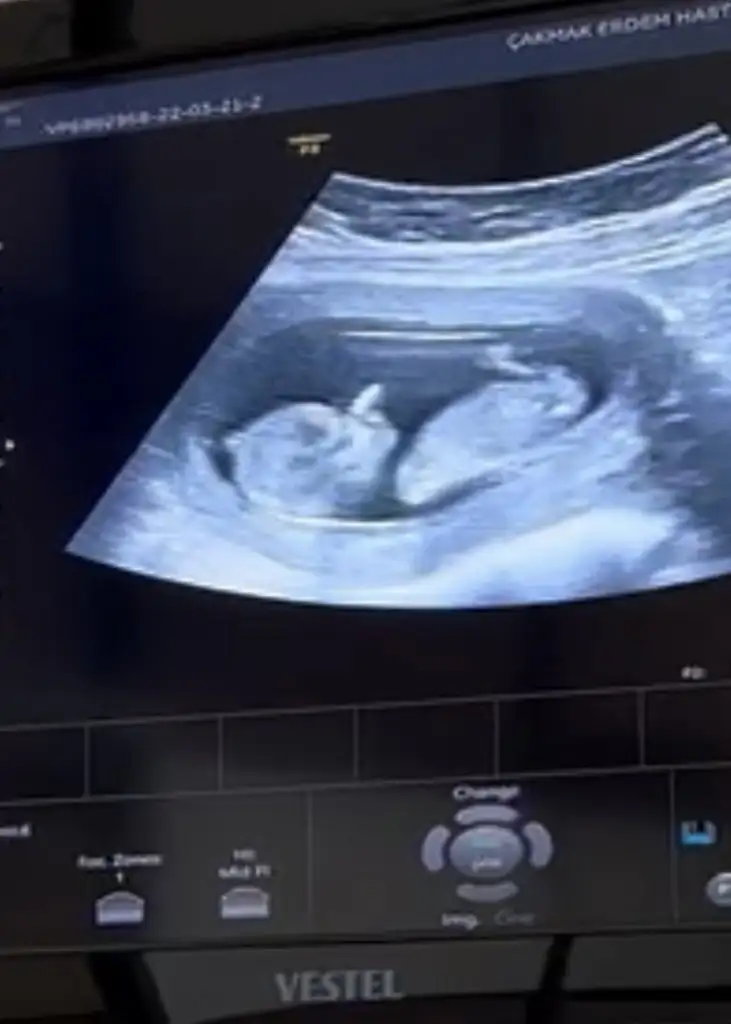

Kız olabilir belki erkek kendini erken belli ediyor sanırım 11+3te görmüştük bizKızlar bizde 12+2 olduk. Doktor cinsiyet için çok erken dedi 3 hafta sonra tekrardan çağırdı. Cinsiyet tahmini yapanlar kimlerdi etiketleyemedim beceremedim :) Eki Görüntüle 3030734

Birazda doktorun ultrasonu ile.alakali benceKız olabilir belki erkek kendini erken belli ediyor sanırım 11+3te görmüştük biz![]()